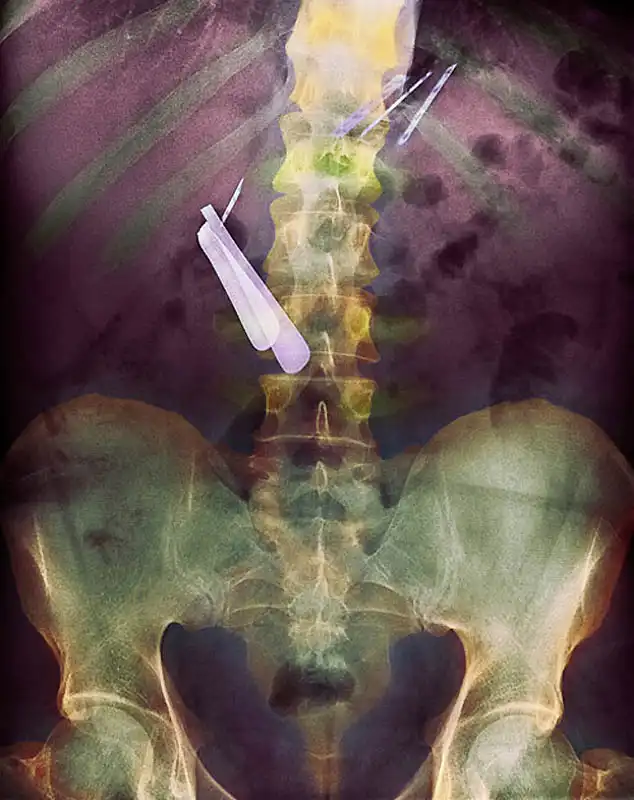

Цветной снимок предметов, которые проглотил пациент, и которые застряли в его кишечнике, включая ложку и лезвие.